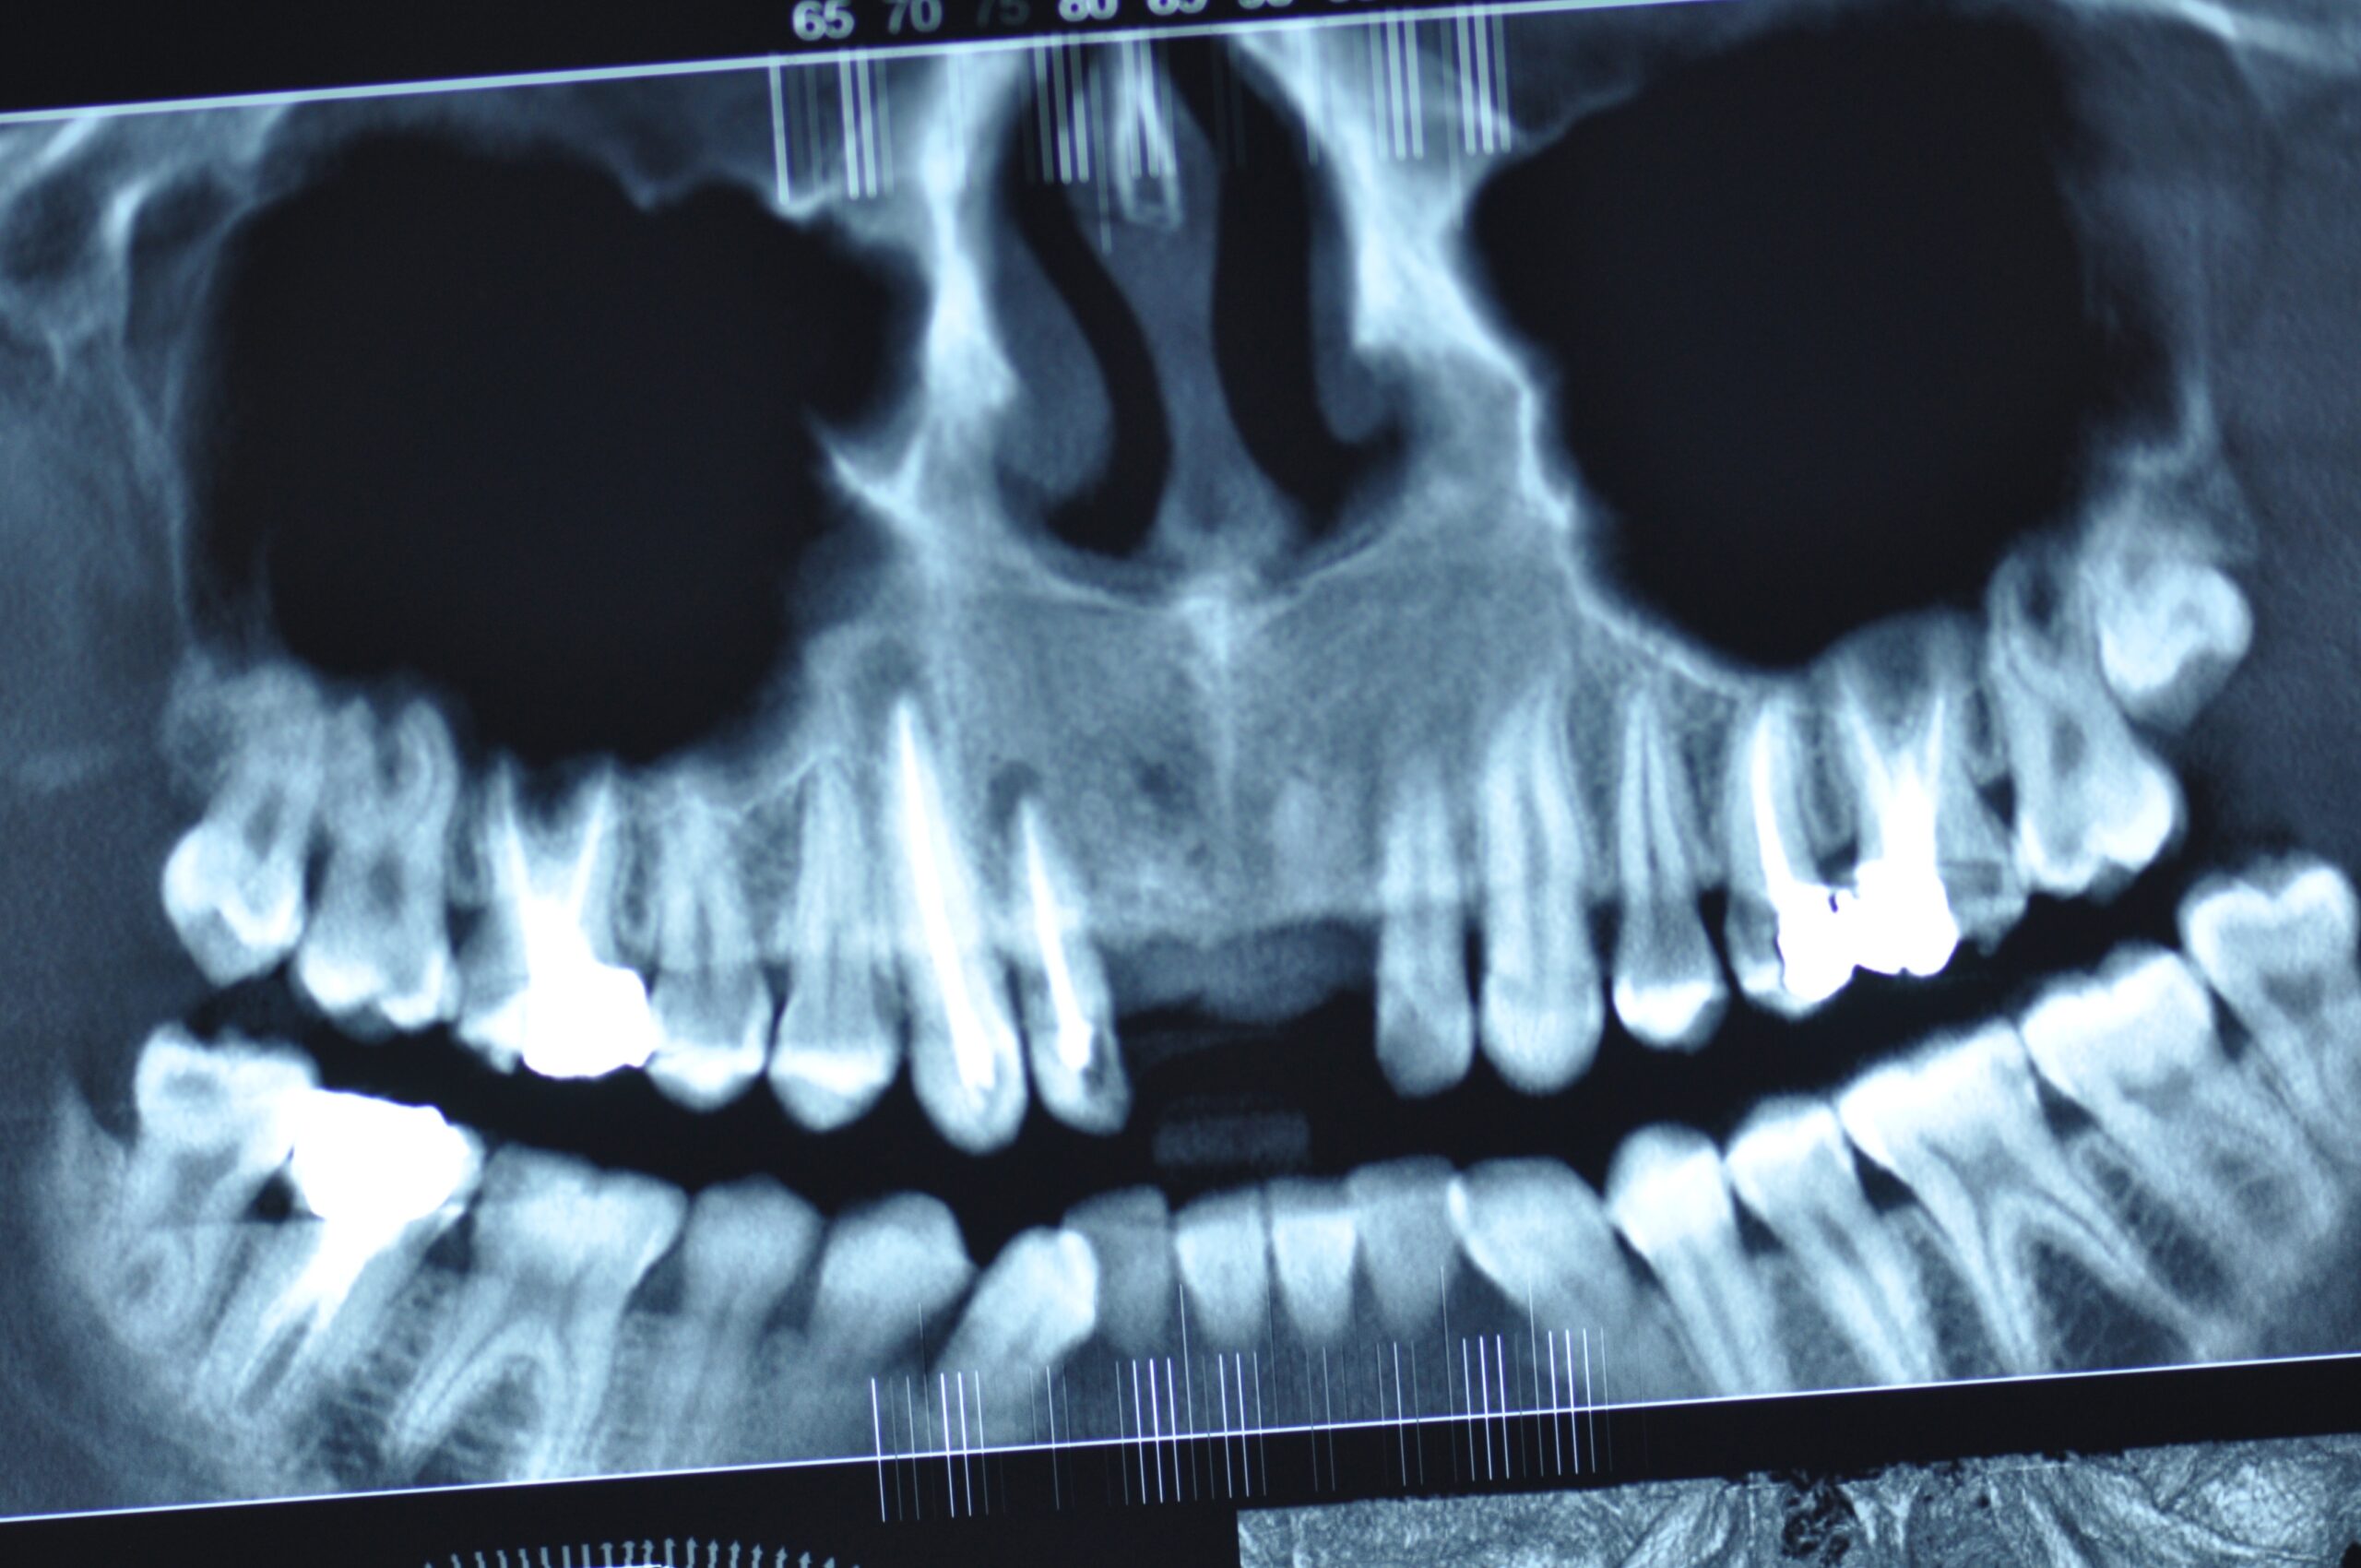

→ Avant l’intervention

Après une étude approfondie de vos antécédents dentaires et médicaux, le dentiste détermine si les implants dentaires sont indiqués dans votre cas. Il examine ce qui doit être fait, se prépare et vous explique en plan de traitement à venir.

La durée totale du traitement dépend de plusieurs facteurs. Il est déterminé en fonction du nombre de dents à remplacer, du volume osseux, de l’état général du patient. En général, il faut entre 3 et 9 mois.